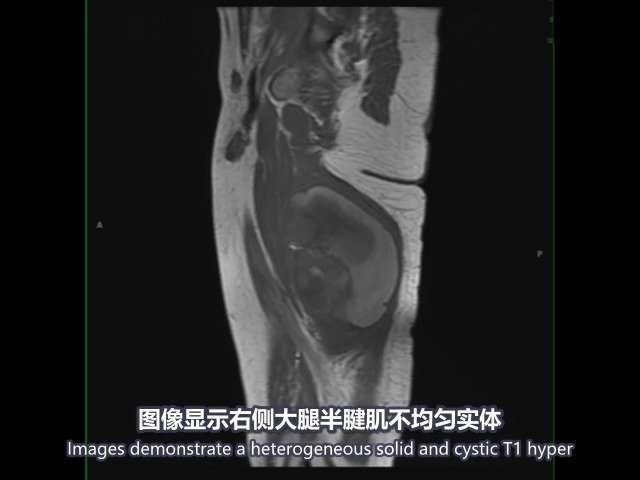

医学双语课程:大腿滑膜肉瘤 synol sarcoma

图片尺寸640x480